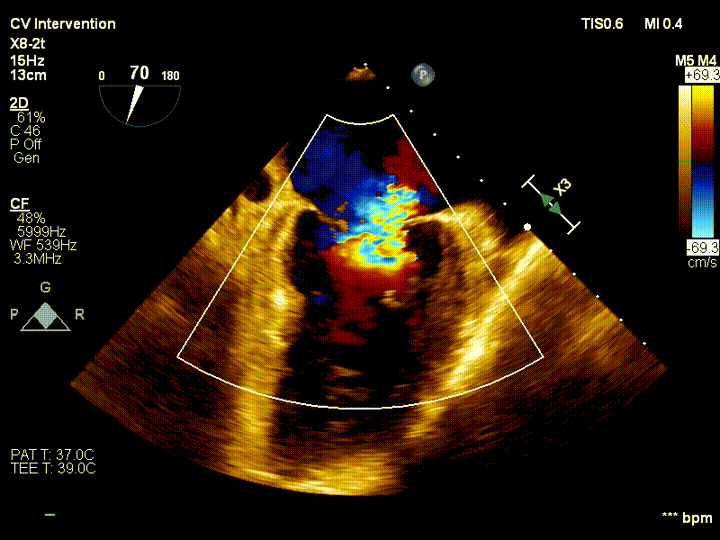

王焱教授团队和美国弗吉尼亚大学医学中心David Scott Lim教授、香港亚心医院林逸贤教授术前详细评估并制定了相应的手术策略,并在手术当天在线指导。在浙江大学附属第二医院王建安书记结构团队核心成员刘先宝主任的现场指导下,王焱院长团队顺利完成股静脉穿刺,然后在食道超声指引下顺利穿刺理想位置的房间隔,肝素化后,放置25F鞘管至左房,测定左房压,随后顺利于二尖瓣前后叶植入两枚二尖瓣钳夹装置,术前患者二尖瓣重度反流即刻减轻至微量,左房压力即刻减低,预示着患者的临床症状将得到明显改善。手术全程用时不到2小时,患者术后即刻拔管苏醒。

本次手术的顺利完成标志着DragonFly™在全国开展的多中心注册临床研究已陆续在各地的顶级医院开展,本研究计划入组上百例二尖瓣反流的患者,并由德晋医疗免费提供DragonFly™二尖瓣修复器械,为入组患者提供二尖瓣反流治疗的优质解决方案及顶级医院的专业医疗服务和术后随访服务。